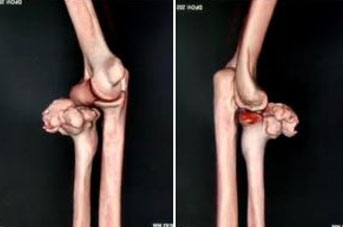

Lesion arising from the anterior cortex of the neck of the radius, measuring about 4.2×3.7 cm, which was projecting toward the anterolateral aspect of the elbow But not involving with humero-radial, humero-ulnar, and proximal radio-ulnar articulation (Figure 3).

Figure 3: CT 3D reconstruction of right elbow.